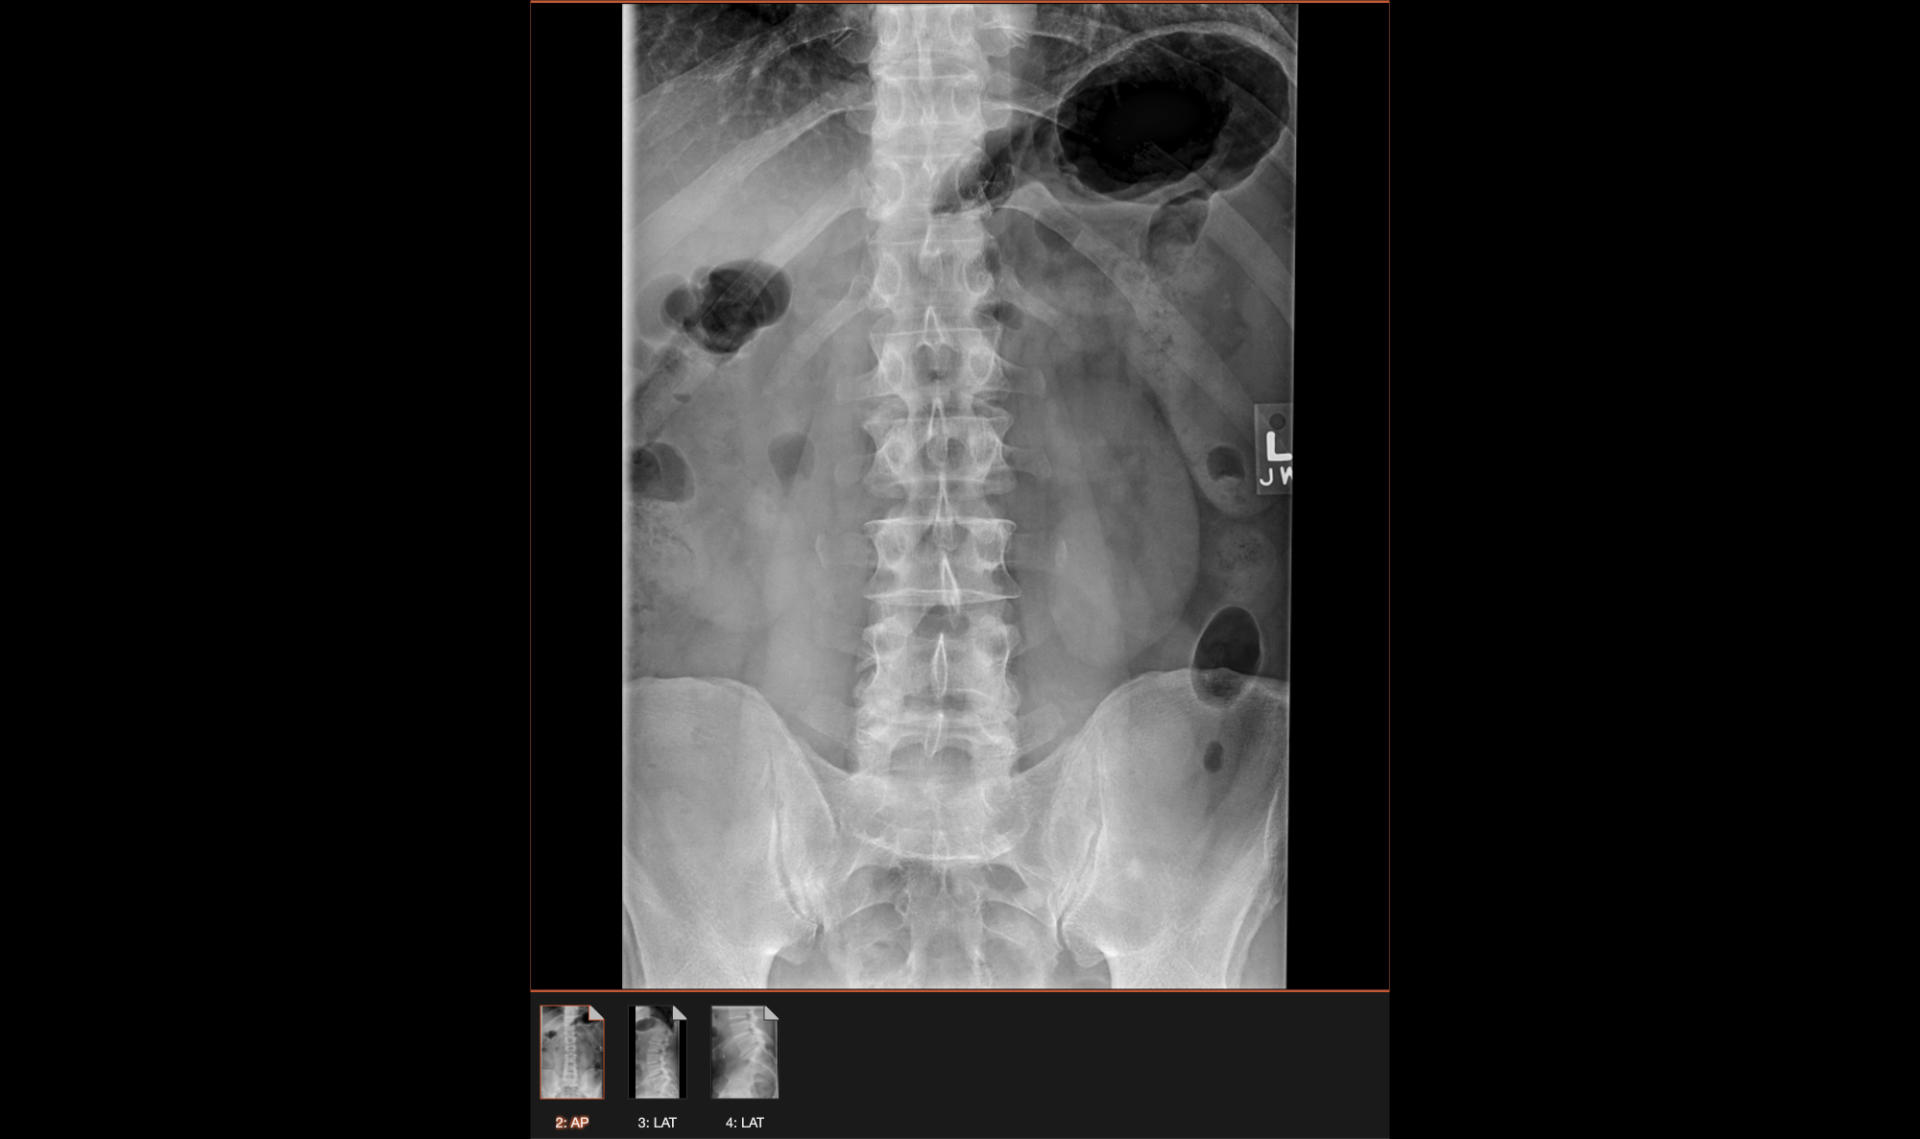

MRI Scan

Oh! A lot has happened since the last post. I saw a doctor, got an injection in my hip (that did not work and offered no relief) and then I got an increase in my medication, and then I got an MRI and then another increase in my medication (sigh) and sometimes I have to take out-of-state medication.

MRI Imaging

MRI Animated GIF file

So what’s next? Well, I got an EMG (electromyography) and the good news is my nerves are not damaged. So I saw another doctor this week and we’re going to move forward with getting me two injections into each side of my spine because they can’t do just one from the back due to the spacing. (Eww.)

The thing about this pain I have now, which was originally diagnosed as sciatica, is that it’s become so unpredictable, and so painful. I guess the discs in my lower back and garbage, and it’s causing nerve pain, and it’s so, so bad. Some days I am in pain for a few hours, and some days it’s 10+ hours. When the pain is gone I am mostly fine, unless I sit in a desk chair for too long. I’ve been doing the “set a timer, sit and work for 20 minutes, then get up to stretch and move” routine for months now.